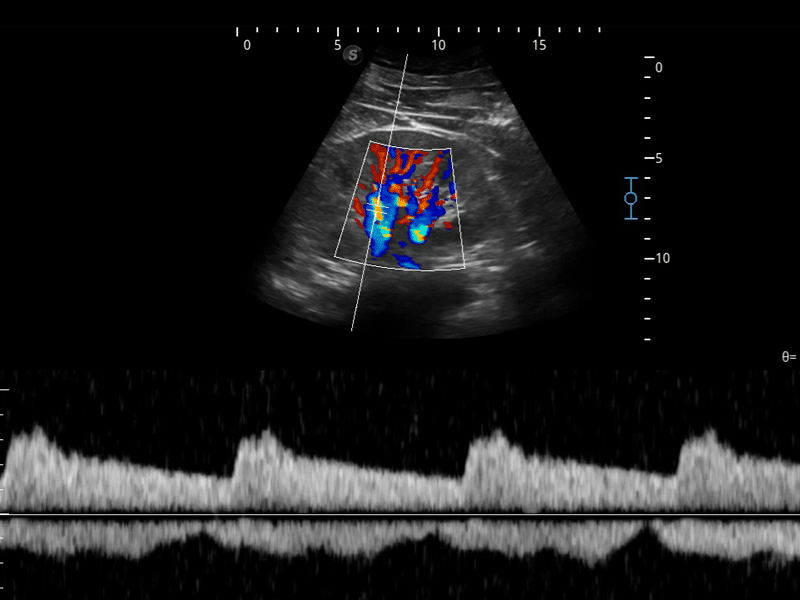

组织多普勒

组织多普勒成像功能,可提供心肌运动速度和其他临床信息,使临床医生能够分析和比较患者心脏不同部位的运动。